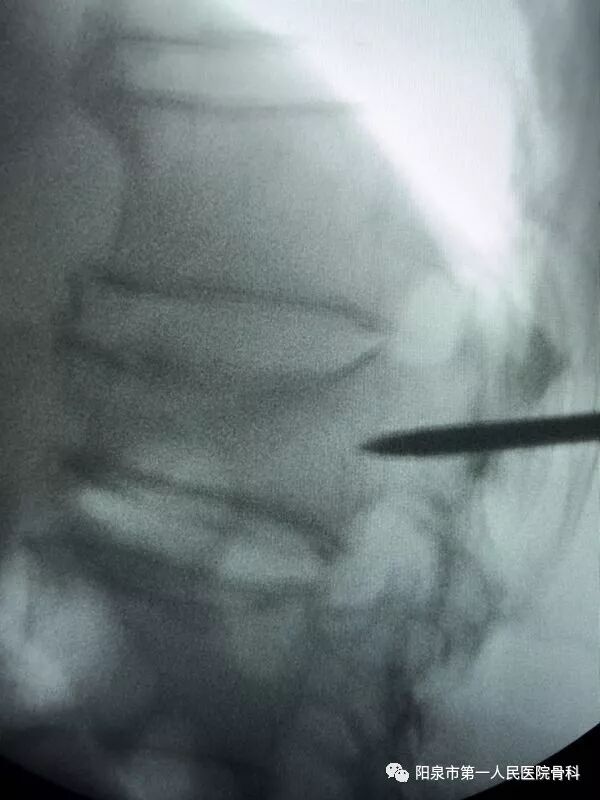

下图为穿刺针已经准确进入到椎体部位

下面为在C臂机透视下观察到的穿刺操作过程,正侧位分别透视来确保正确的穿刺部位。图中黑色直杆为穿刺针。